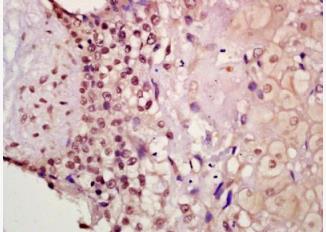

Rabbit Anti-Phospho-Smad2 (Thr220) Polyclonal Antibody

Target Protein:Phospho-Smad2 (Thr220)

IHC-P(1:100-500)